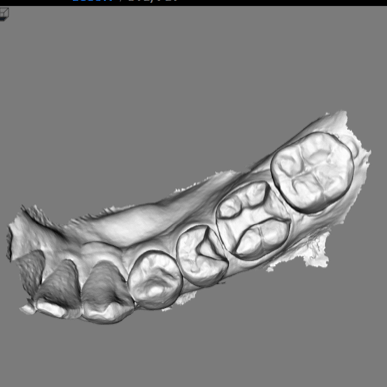

口掃機(口腔掃描機)就是用小型鏡頭,在嘴巴裡快速拍攝上百張照片,拍攝速度像機關槍一樣,再用照片堆疊出立體的3D圖,整個過程大約兩到三分鐘,接著就可以在電腦裡看到自己的牙齒模型了,許多患者看到時,都會訝異現今科技的發展。

我個人覺得口掃機最有意思的是,掃描當下就可以看到自己的牙齒,以3D圖繪製在電腦螢幕上,平常自己看不到的地方也都一清二楚,相當新奇。

也可以藉此知道上下牙齒是怎麼咬合、哪些死角是需要加強清潔等等,眼見為憑,沒看過還不知道自己牙齒是長這樣呢!